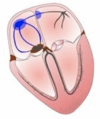

List the excitable varieties of cardiac tissue

- Pacemakers

- Conductive system

- Working fibres

Purpose of the Aschoff-Tawara (AV) node

Delays the atrial signal

So atrial contraction precedes the ventricular contraction

Pacemaker cells

- Located: SA / AV node

This electrical activity is expressed in…

Sinoatrial (SA) node